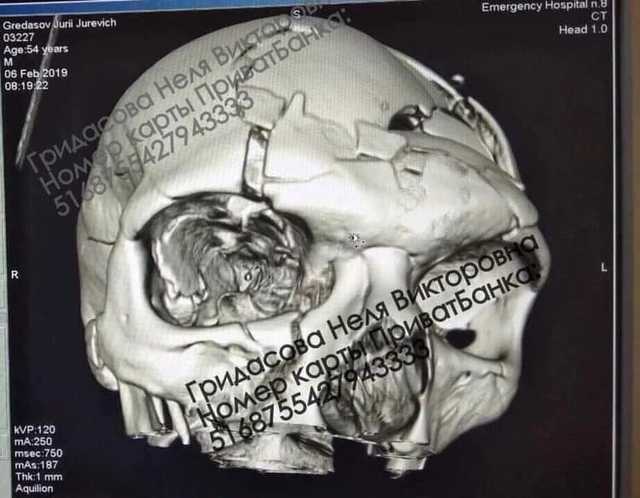

В Каменском жестоко избит известный хирург: разбита половина черепа

На онкохирурга из города Каменское Юрия Гридасова совершили нападение, которое могло привести к смерти. Об этом сообщил знакомый врача, старший инструктор по тактической медицине Международного проекта «Центр подготовки Patriot» Денис Сурков в Facebook.

Он рассказал, что Гридасов выходил из машины, когда на него напали неизвестные и дважды ударили по голове тяжелым предметом —  трубой или битой. В результате у пострадавшего разрушен череп. Ему сделали операцию в днепровской больнице имени Мечникова, удалив обломки костей, очаги кровоизлияний и контузии. Также ему сделали пластику свода черепа титановой пластиной.